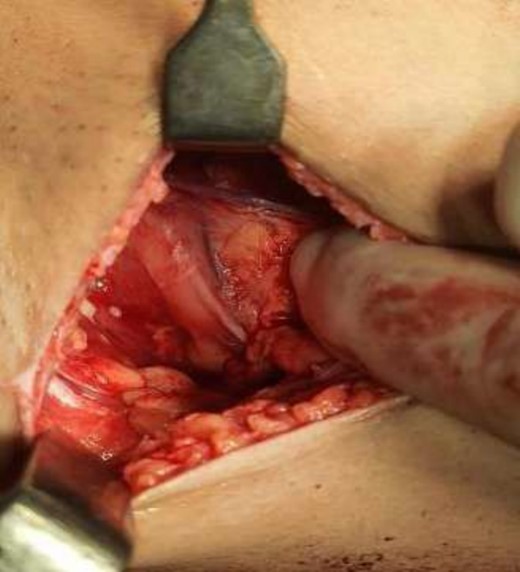

The operating surgeon opted for a vertical mastopexy to remove the mass and simultaneously reconstruct the breast to restore it as much as possible and to have a cosmetically better scar (Fig. 7). The skin was marked, a peri-areolar ellipse having a diameter of about 15 cm was made that extended vertically below, 4 cm above the inframammary fold. The skin was dissected along the incision line and the mass was removed. Grossly, the specimen measuring 5 × 3.5 × 3 cm3, containing the firm mass, was sent for histopathological analysis. Axillary lymph node biopsy was done. Two drains were placed, and the skin was closed in the form of a superior circle and an inferior ellipse (Figs 3–6).

Mastectomy procedure (Elliptical Incision given around nipple).

Mastectomy along with sentinel lymph node biopsy procedure (Tumor Approach).

Mastectomy along with sentinel lymph node biopsy procedure (Sentinel Lymph node Biopsy).

Mastectomy along with sentinel lymph node biopsy procedure (Tumor extracted).